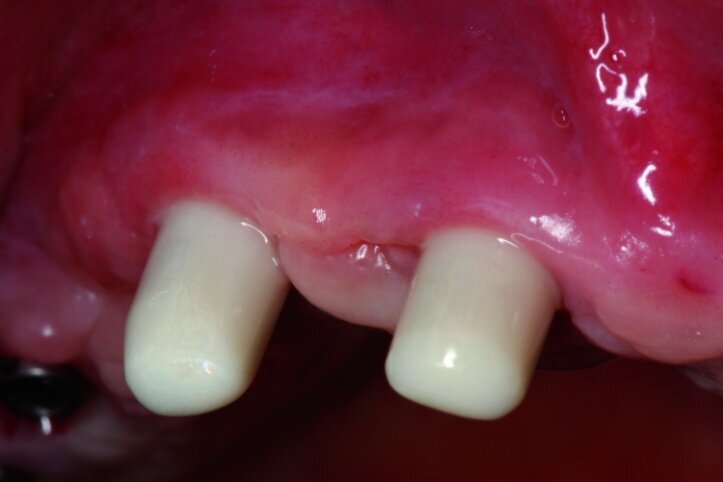

Each treatment should start with a well-prepared plan. For most patients appearance after treatment will always be very important that is why an intraoral analysis must be made in order to assess the static structure of the mouth, as well as an analysis of the lips’ dynamics along with teeth exposure during speaking and smiling (Figs. 1 & 2).

We analysed the aesthetic aspects in a way that enables us to reach an optimal balance between white (teeth) and pink (gums) aesthetics. Of course, in toothless patients, one should take note of the fact that teeth setup as well as reconstruction of atrophied tissues will constitute a support for the lips. Such an analysis may be made on the basis of a restoration that the patient uses. In this case, first sanitation of the maxilla had to be performed, next a temporary acrylic prosthesis was made.

In the next phase, implants were inserted. In compliance with the results of the CBCT study, a sinus lift procedure was performed with a simultaneous implantation in the region of lateral teeth. Eight Ankylos implants were introduced, raising both maxillary sinuses at the same time. After six weeks, the implant exposure procedure was performed. Because of the fact that implants were partially anchored into the bone at the lateral section, partially within the augmentation material while primary stability was achieved, we decided to expose implants at lateral sections without occlusal load so as to perform the so-called bone training with a view to improving the condition of the bone being regenerated. An impression was taken (Figs. 7 & 8) for the positional model and for the preparation of the temporary prosthesis based on telescopes.